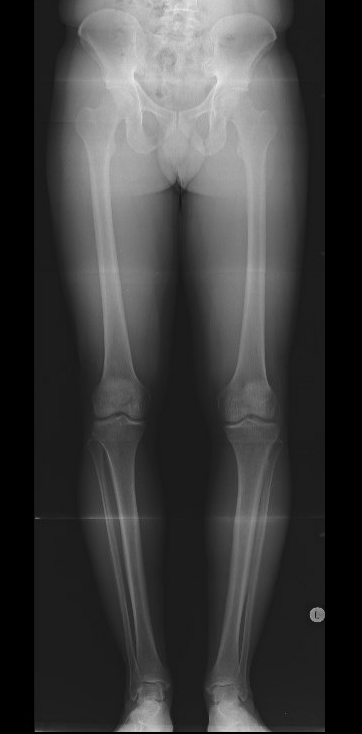

Example of medial cartilage procedure

- anatomical angle 0o

- correct to 5o valgus

- need to correct 5o

Measure anatomic femoral tibial angle